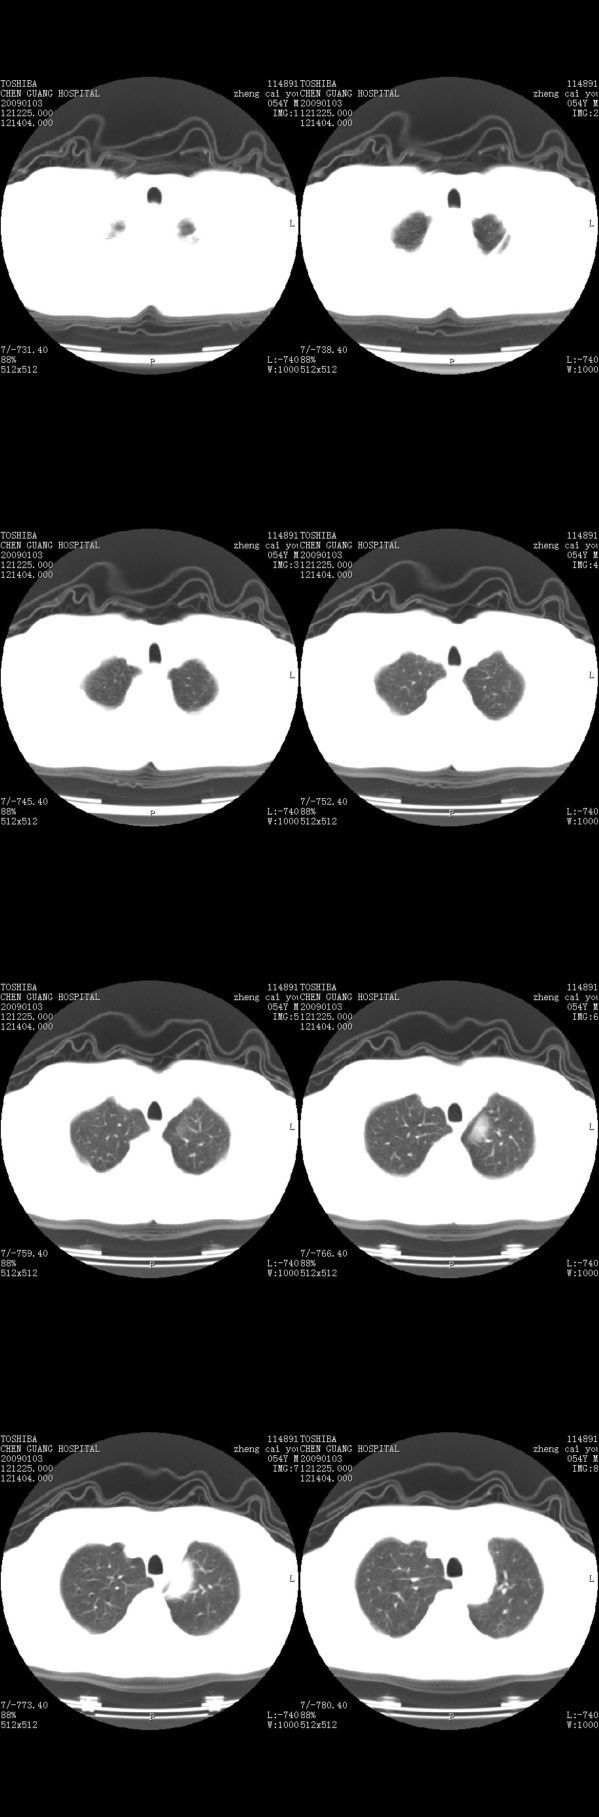

男,54岁,平时有吸烟后咳嗽、咯痰史,因右侧胸部(腋窝下)疼痛来检查平片,见右下肺动脉干起始处处结节,后到同学处做了平扫及增强。请各位老师帮忙看一下,不甚感谢!!!!!

支气管壁增厚

右肺下叶支气管扩张。

顺序确实有点乱,不过在右肺上叶后段近气管旁仍可见一结节灶,希望楼主小心观察分析。

考虑------支气管壁增厚---局限性气肿---建议----气管镜进一步检查

小叶中心型肺气肿

增强了 但纵隔窗调的看不清  右上叶支气管壁似有增厚 警惕

肺窗薄扫、常规扫描均未见明确病变;右下肺门圆形与肺血管等密度影,考虑为血管变异;应该要纵隔窗才能进一步明辨。

右肺上叶前后段支气管夹角处可见一结节影,图像资料不全,不好下结论。